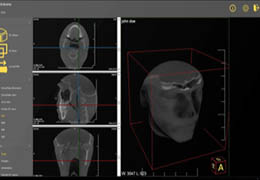

ANYTHINK 经导管主动脉瓣膜置换术分析系统